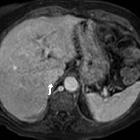

Isolated

intracaval recurrence of resected renal carcinoma. Unenhanced T2- (a-d) and T1-weighted (e) images showed tumour thrombosis in the intrahepatic vena cava (arrows) and normal flow-void signal at the hepatic vein confluence (arrowheads).